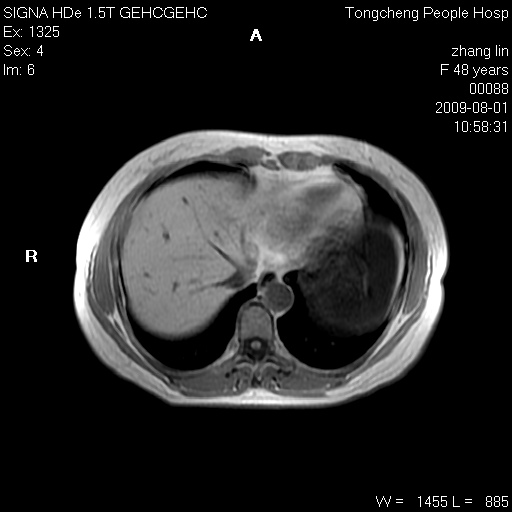

女,48岁。健康体检,彩超发现右肾占位性病变。平素健康。

临床诊断:右肾占位性病变,性质待定(囊肿?肿瘤?)。

上中腹部mr平扫+增强扫描,图像如下:

右肾上极见一类圆形病灶,t1wi呈等信号t2wi呈等高混杂信号,三期增强无强化,边界清---考虑囊肿出血。

同反相位均表现为等信号,病变无强化,考虑含蛋白的囊肿可能,弥散加权相或许有些帮助,

慢性胆囊炎